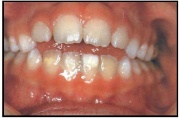

Vali sind huvitav pilt ja me näitame sellega seotud haigust ja sümptomeid